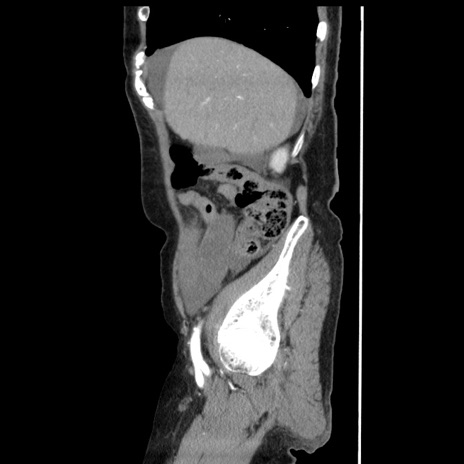

横断像

【症例】80歳代女性

【主訴】腹痛

【現病歴】8時間前から腹痛あり来院。

【既往歴】糖尿病、脂質異常症、子宮体癌にて子宮全摘術

【身体所見】意識清明・会話良好だが腹痛で苦悶様、全腹部にわたって反跳痛と圧痛あり

【データ】WBC 13600、CRP 0.14、LDH 224、CK 90